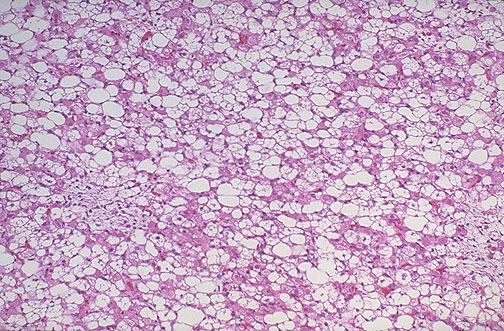

Cell of origin in liposarcoma

Cellular feature of neoplastic cells

Adipocyte

Pleomorphism of lipoblasts

Microscopic feature of liposarcoma

Preferred treatment of sarcomas

Response of sarcomas to chemo/radiation

Large bizarre lipoblasts